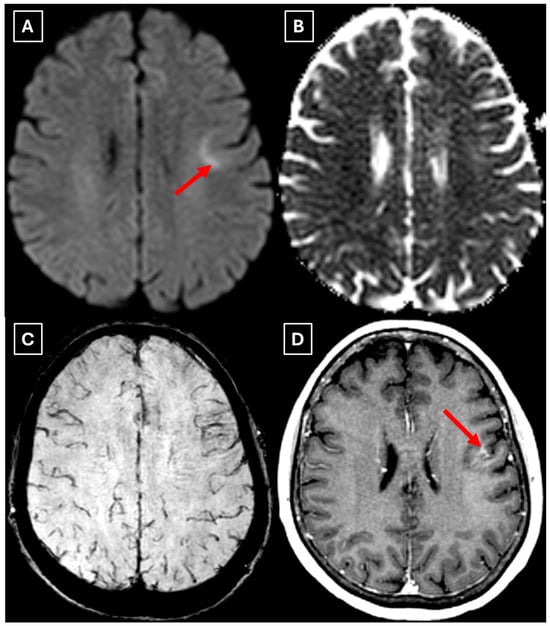

Figure 3. MRI scan of the brain. (A): Axial trace image of diffusion-weighted imaging (DWI) shows slight diffusion restriction in the lesion wall when correlated with (B): dark signal on apparent diffusion coefficient (ADC) maps in the wall of the lesion, with no central diffusion reduction observed. (C): In the corresponding axial slice of the susceptibility-weighted imaging (SWI) sequence, there is no evidence of blood products within the lesion. (D): On the axial postcontrast T1-weighted imaging, there is no contrast enhancement in the lesion, although a central vein-like structure is observed. Red arrow—diffusion restriction, yellow arrow—perifocal vasogenic edema, green arrow—central vein sign.

Figure 5. Two-week follow-up MRI axial scan of the brain. (A): Axial trace from diffusion-weighted imaging shows a higher signal along the peripheral parts of the lesion with the absence of cytotoxic edema when correlated with (B): the ADC map. (C): Central vein sign is positive on the susceptibility-weighted imaging sequence and (D): axial postcontrast T1-weighted sequence. These findings were not typical for low-grade astrocytomas. Red arrow—diffusion restriction, yellow arrow—perifocal vasogenic edema, green arrow—central vein sign.

There are no pathognomonic features for tumefactive demyelinating lesions, but there are still some MRI findings that support the diagnosis. TDLs appear larger than 2 cm and are most often located in the frontal or parietal regions. The supratentorial white matter, especially in subcortical and periventricular locations, is commonly affected. On T1-weighted images they usually demonstrate hypointensity and hyperintensity on T2-weighted images, consistent with demyelination. These lesions have a varying degree of perifocal edema and mass effect, but both are usually mild relative to the lesion size in comparison to neoplasms or abscesses. The most characteristic enhancement pattern is the open-ring (incomplete rim) enhancement, which is significantly more common in TDLs than closed-ring enhancement. The open ring typically faces the cortex or gray matter and is considered a strong supportive feature for TDL diagnosis [3,11,18]. Contrast enhancement is not a universal feature, as Lucchinetti et al. (2008) [1] reported that approximately 5% of TDLs on postcontrast T1-weighted MRI did not show enhancement in their study. This finding was also observed in this case (Figure 3D), as well as in the case presented by Zafar et al. (2022) [19]. Therefore, the absence of enhancement does not necessarily exclude a demyelinating pathology.

Another MRI feature strongly associated with TDLs is a central vein sign (CVS), which was also observed in this case (Figure 3, Figure 5, and Figure 7), currently being considered for inclusion in MS diagnostic criteria. On SWI or T2-weighted sequences, CVS appears as a thin hypointense line or dot less than 2 mm in diameter, visible in at least two planes, and running partially or completely through the center of a lesion [2]. Although most studies of the CVS have focused on MS and radiologically isolated syndrome, the CVS is also applicable for TDLs, representing an atypical variant of MS. In radiologically isolated syndrome, Suthiphosuwan et al. (2019) [21] reported a median of 87% CVS-positive lesions per case, underscoring its strong association with inflammatory demyelination [2]. In the TDL cohort described by Ongphichetmetha et al. (2024) [2], CVS was observed in approximately half of the patients, while open-ring enhancement occurred at a similar frequency of around 50%, with both features supporting an inflammatory demyelinating rather than neoplastic process.

We also found similarities between this case and the classical imaging features of TDLs described in the literature. Hypoattenuation on noncontrast CT corresponding to enhancing areas on MRI is another useful imaging finding in TDLs [10], which may be explained by the tissue rarefaction caused by the active demyelination rather than increased cellularity, which is seen in tumors, thereby supporting the use of MRI with noncontrast CT in TDL diagnosis. Furthermore, restricted diffusion along the lesion margin with elevated central ADC values, in contrast to neoplasms which more commonly show central diffusion restriction, have been described as a commonly presenting feature of TDLs [3,4,10], which was also observed in this case (Figure 5A,B).

In this case, despite the presence of a T2/FLAIR mismatch sign (Figure 2), several imaging characteristics were more suggestive of a TDL rather than IDH-mutant astrocytoma. The lesion was located in juxtacortical white matter and had cortical sparing, which is unusual for IDH-mutant astrocytomas, since they typically have been shown to infiltrate and expand the cortex. The diffusion restriction at the lesion margin with centrally elevated ADC values was more consistent with reported DWI findings of TDLs and contrasted with the central restriction often seen in gliomas. The mass effect was mild in comparison to the overall lesion size, favoring demyelination rather than neoplasm in this case. Additionally, the lesion had a central vein sign, as described above, a radiological sign supportive of inflammatory demyelination. The combination of cortical sparing, peripheral diffusion restriction, mild mass effect, and the appearance of central vein sign represented strong features that raised suspicion of a tumefactive demyelination lesion.